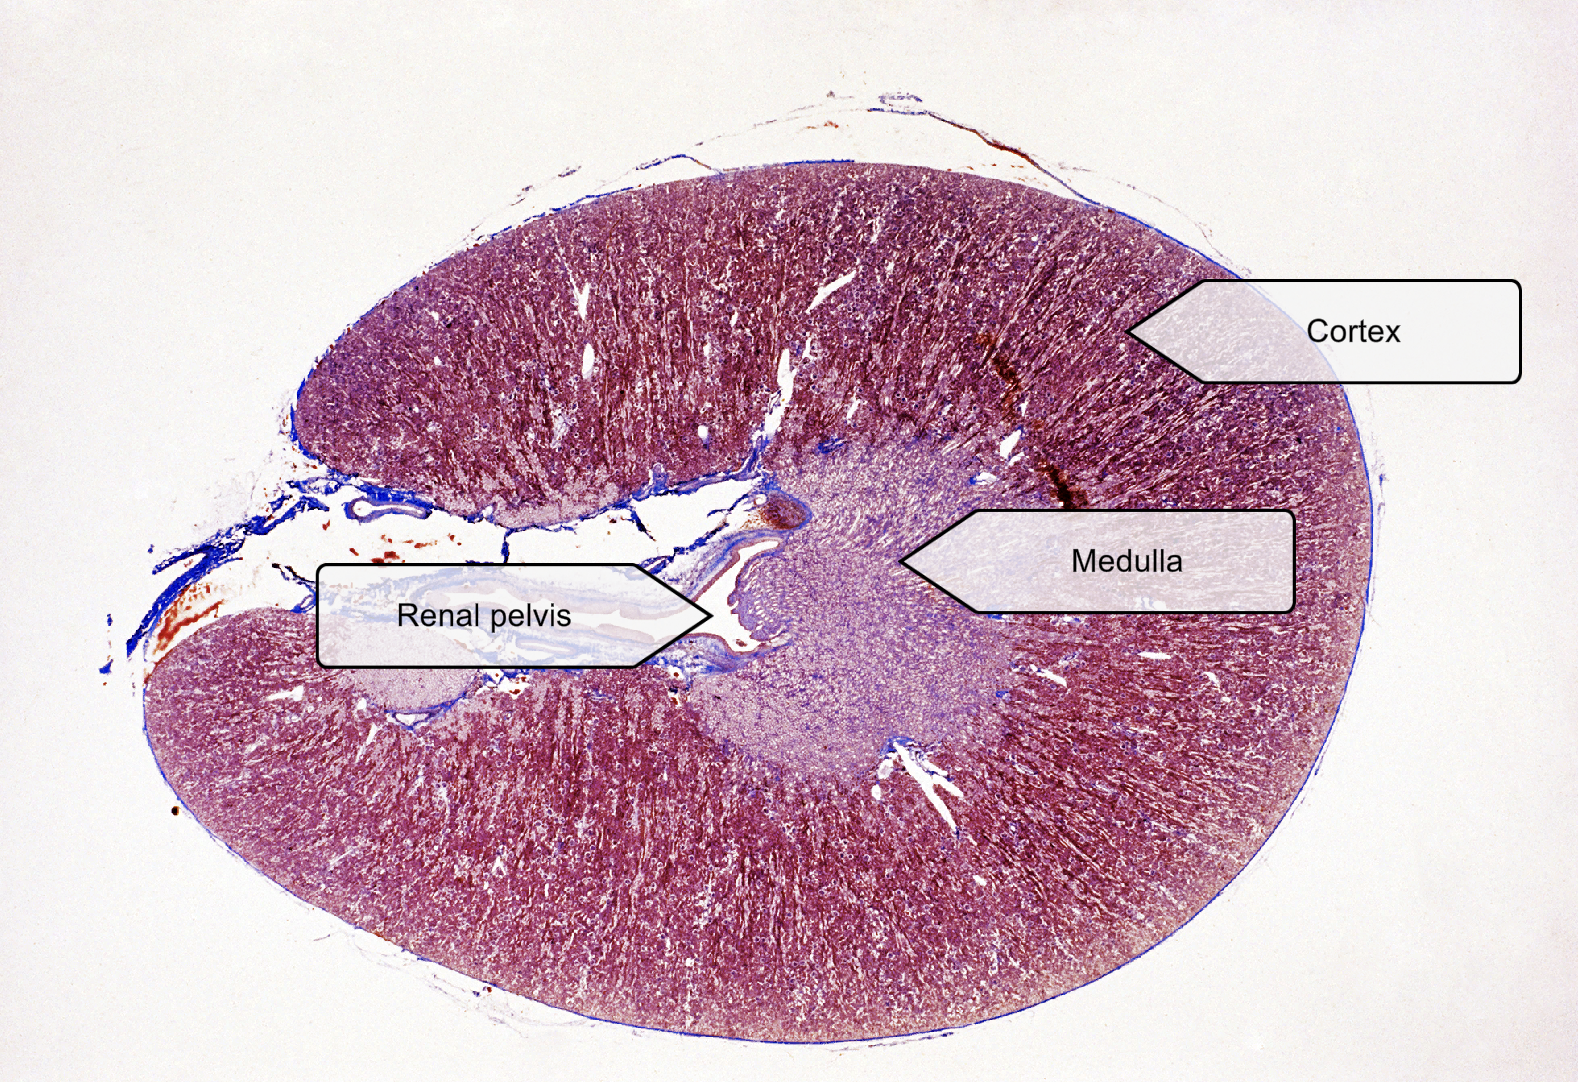

List layers of Kidney (Low magnification view)